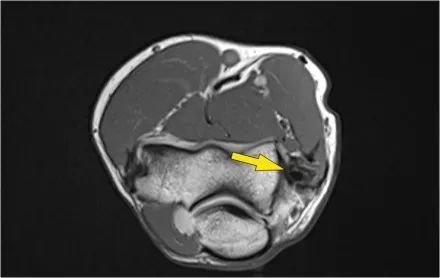

MR-关节造影证实了骨软骨病变。在肱骨和骨软骨病变之间存在钆造影剂,这表明它是不稳定的。注意轴向图像上看到的碎片。